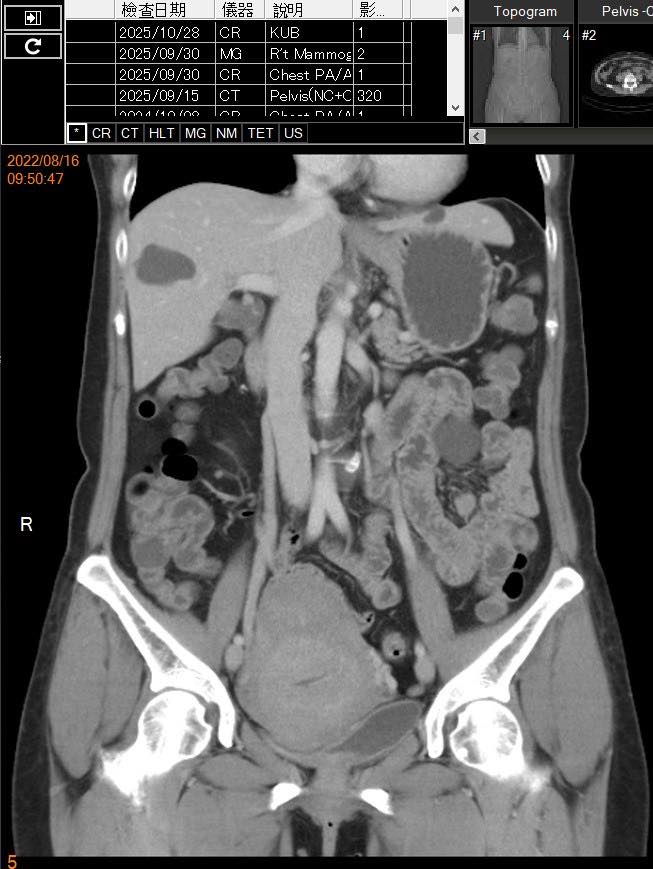

肿瘤科医师邱德生近日透过社交平台分享这起门诊个案,说明这名患者在2022年8月被确诊为子宫内膜癌第一期(IA期、Grade 1),随后接受微创手术,病灶已完整切除。术后免疫染色结果显示雌激素受体(ER)阳性、黄体素受体(PR)阳性、p53表现正常、错配修复系统(MMR)完整,经多专科肿瘤团队评估后,认为手术治疗已达充分效果,无需追加放疗或化疗,仅安排定期追踪。

在此之前,该患者曾于不同阶段被诊断为乳癌第一期,并接受Tamoxifen药物治疗三年;此外,她也曾因甲状腺癌接受手术治疗。三次癌症诊断均发生在不同时间点,治疗路径各异,但均依照标准流程完成。

目前,患者整体健康状况良好,ECOG功能评分为0,影像检查、肿瘤指标及理学检查皆未显示复发证据,医学评估为完全缓解(CR)并处于无疾病状态(NED)。她偶尔因腹胀、便秘或皮肤搔痒等症状回诊,但相关检查均与癌症无直接关联。